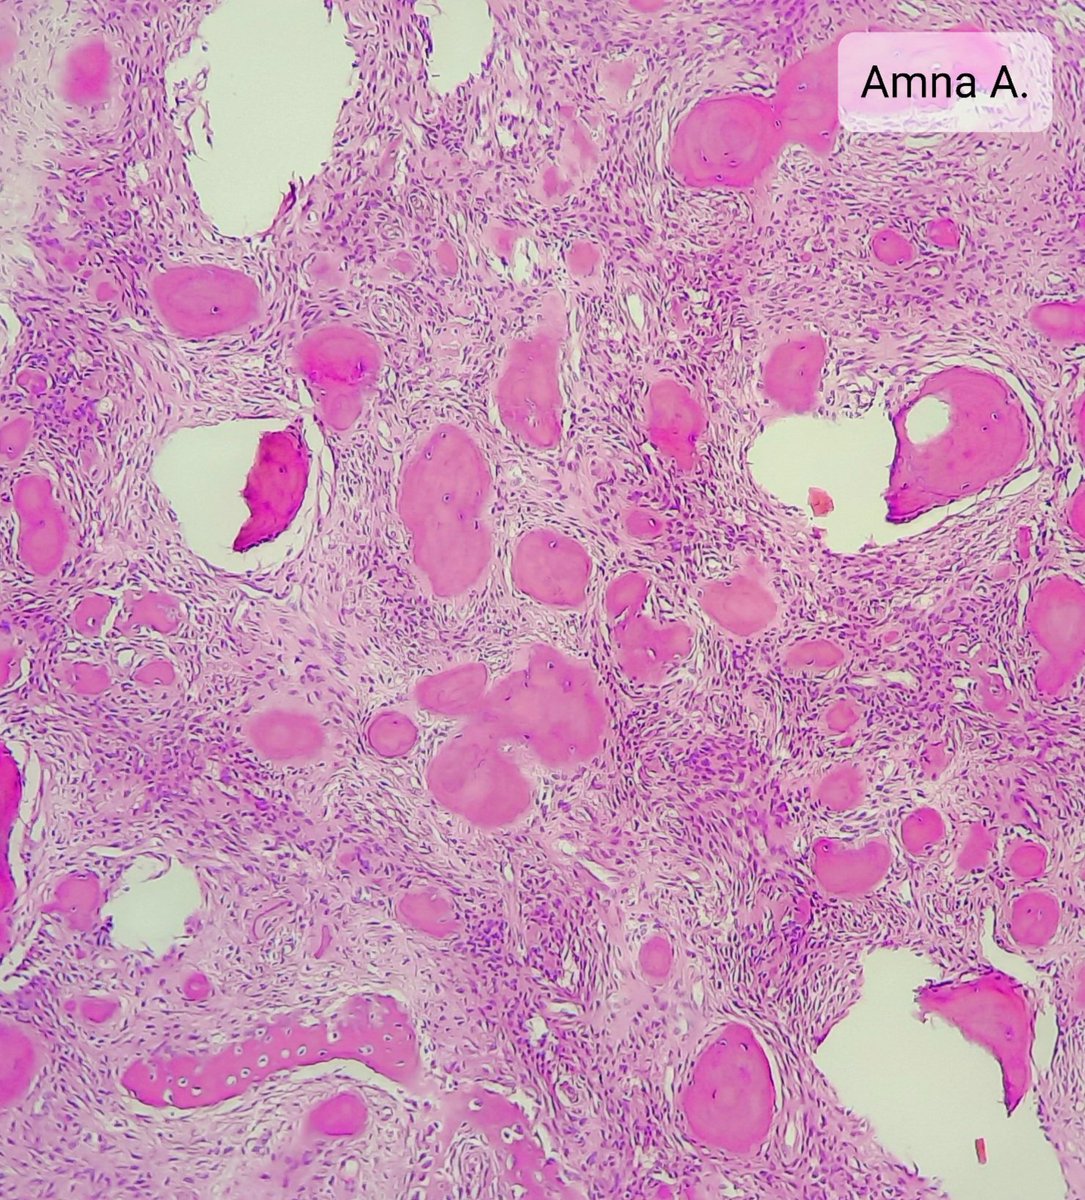

4.3 cm renal mass confined to kidney, tumor cells are predominantly with proliferative, tubular pattern 🎨 CK7 positive (strong, diffuse) 🎨 CD117 negative Thoughts? Sean R Williamson MD Kiril_T_Can Michelle_Hirsch (Donovan) Priya Rao, MD Ankur Sangoi

Kidney, young F adult #gupath Dr. Luca Olaleke Folaranmi Aurélien Morini, MD, MSc 🇫🇷🇪🇺💙💛 Celina Stayerman MD 🔻Nusrat Zahra🔻🇵🇸 @miss_me1986 Gonzalo De Toro Tristan Rutland MBBS FRCPA IFCAP Anandi Lobo, MD Sumanta Das Lorand Kis Erik Kouba bansar Carlos Miguel Ruiz Carlos Nieves Padma Priya J Susan Prendeville @AkgulMd Ankur Sangoi Barry McGinn